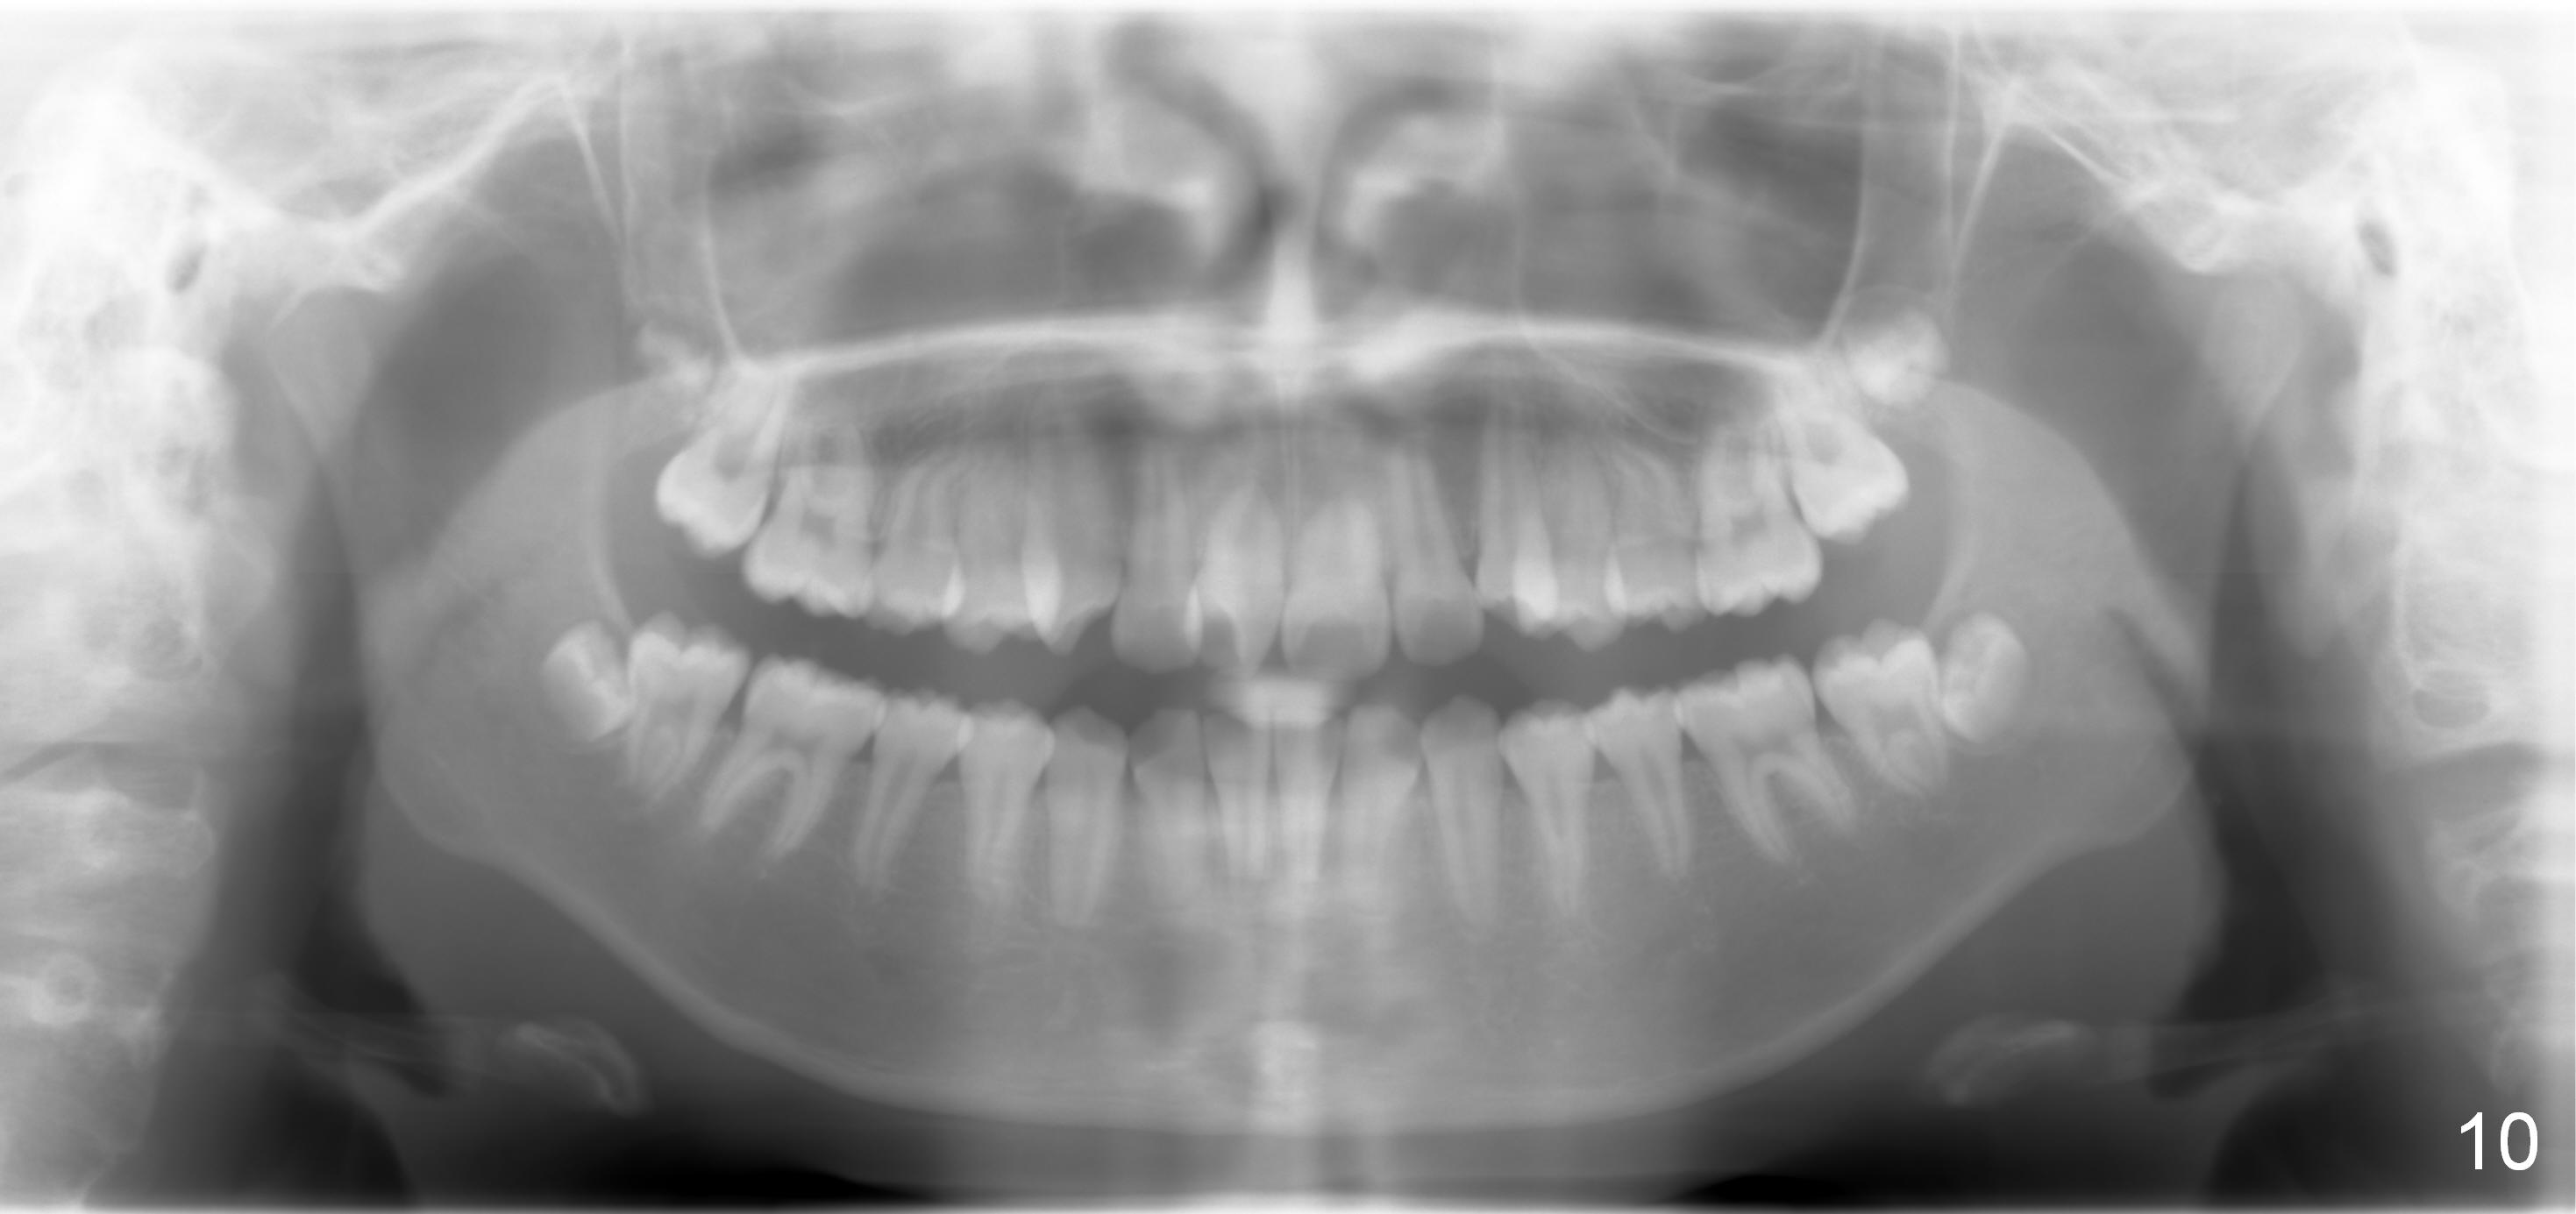

A 13-year-old girl presents for orthodontic consultation.  Chief complaint is crooked teeth.  Her brother is finishing 4 extraction ortho.

Fig.11 is ceph tracing, whereas Fig.12 is clinical, ceph and model summary.

Looking at the records, the lower incisors are protrusive and have crowding, so think extraction.  There is enough combined crowding and class II to warrant extraction.  Since there is lower crowding, it would be 4 bicuspid extractions with the sliding mechanics using elastics or Niti closing coil springs. Closing the extraction space by maintaining the lower incisor position and moving the lower molars forward.  The upper arch is 50/50 front going back/back coming forward. Dr. Doug Ness, March 13, 2015 1:18 AM